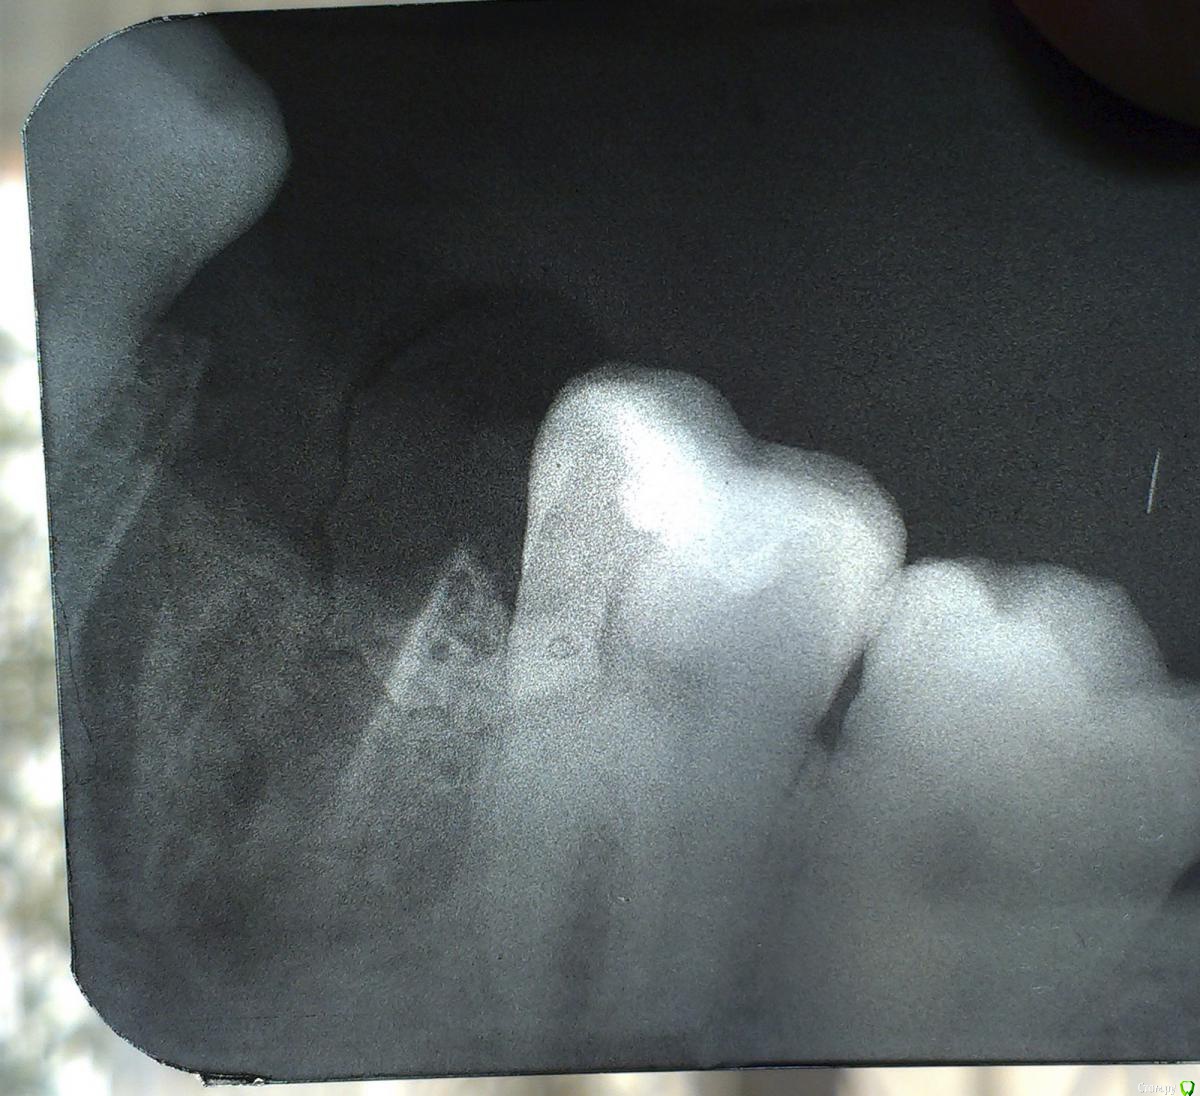

Scream Опубликовано 19 мая, 2015 Автор Поделиться Опубликовано 19 мая, 2015 Уважаемые доктора! Я снова к вам... Позвольте спрошу прямо тут, не плодя свои темы. Спасибо Болит другой зуб, сверху, над удаленным (тоже шестерка). Два месяца назад в нем был залечен хронический пульпит. Снимок ни до, ни после лечения сделан не был. Последние пару недель этот зуб поднывал, но я списывала это на удаленный снизу (думала, что просто отдает вверх). Сегодня, после горячего супа, чуть на стену не полезла - аццкая боль. На холодное не реагирует, при нажатии/надкусывании не болит. Но ноет периодически и на горячее реагирует сильно. Сбегала на снимок - по снимку мне сказали, что все в порядке. Каналы герметичные, дескать, все ровненько. Очень близко гайморовая пазуха. Предложили перелечить за приличную сумму, либо идти туда, где 2 мес назад его уже лечили. Увы, выбрала второй вариант из-за полного финансового аута.И вот сейчас меня черт дернул залезть в интернет. Дело в том, что этот зуб мне лечил зубной врач. Не стоматолог, а именно зубной врач. И в инете я прочла, что зубной врач вообще осложненными случаями заниматься не должен, только кариес (а пульпит, я так поняла, именно осложненный случай). Скажите, это действительно так - зубной врач не должен был этим заниматься?(( Лечила в поликлинике, рядом с домом. Первый раз в своей жизни (обычно хожу в "проверенные" места).И еще вопрос: может ли по снимку все быть в норме, а проблема есть? Почему реакция именно на горячее?К сожалению, снимок снова мелкий и ужасного качества, извините - у нас только такие делают. Но, может, есть какие-то комментарии? Что мне делать? Спасибо вам большое. Зубная боль меня уже настолько измотала, что мне кажется, что это не закончится никогда Ссылка на комментарий